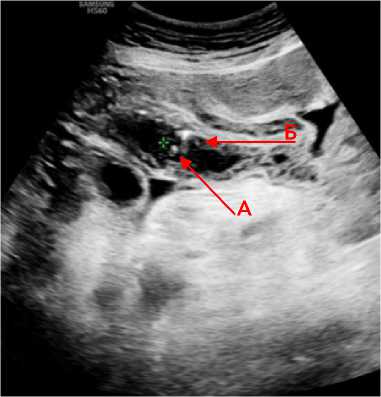

На 3–7 сутки с момента поступления в стационар у трёх пациентов при УЗИ на фоне пареза кишечника выявлены изменения со стороны тонкой кишки: лоцировался спазмированный фрагмент тонкой кишки без перистальтики, распластанный на инфильтрированной брыжейке повышенной эхогенности, в режиме ЦДК кровоток в брыжеечном крае тонкой кишки не получен (рис. 2). В других отделах брюшной полости петли тонкой кишки умеренно расширены, в просвете с жидкостным содержимым, складки слизистой прослеживались, перистальтика не определялась, ткани брыжейки средней эхогенности слоистой структуры.

Рисунок 2. Эхограмма фрагмента тонкой кишки ( А ), распластанной на инфильтрированной брыжейке ( Б ) – воспалительный инфильтрат с вовлечением брыжейки и фрагмента тонкой кишки Figure 2. Echogram of a fragment of the small intestine ( A ), spread on the infiltrated mesentery ( Б ) – inflammatory infiltrate involving the mesentery and a fragment of the small intestine

В поздние сроки (7–21 сутки) в трёх случаях лоцировался фрагмент тонкой кишки с отёком стенки пониженной эхогенности с мелкими гиперэхогенными включениями в структуре – пузырьками газа (рис. 3).